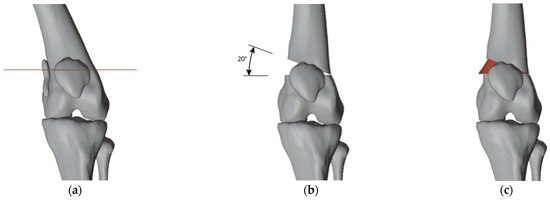

2.3. Surgical Simulation and Planning